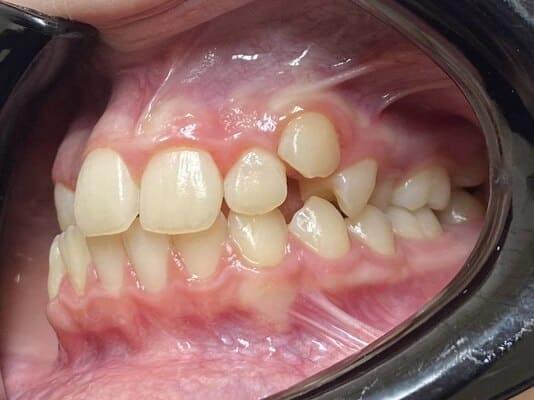

Пацієнт 2 років, уражено десять зубів, шість із яких потребують покриття коронками. В зв’язку зі значним об’ємом та складністю лікування прийнято рішення про лікування в умовах анестезіологічного забезпечення. Раніше була спроба пролікувати ці зуби застарілими методами, які не тільки не є ефективними відносно лікування, а ще і додають дитині комплексів через характерне фарбування зубів. Через високи естетичні вимоги дитини і батьків було прийнято рішення покривати естетичними цирконієвими коронками, як передні так і бічні зуби. Через 2,5 години дитина без інфекції в порожнині рота, з відновленим здоров’ям та естетикою посмішки може кусати, жувати, посміхатись без болю та дискомфорту. Останнє фото через 2 роки після лікування, оскільки естетичні коронки в дитячій стоматології - це надійність, естетика та функція.